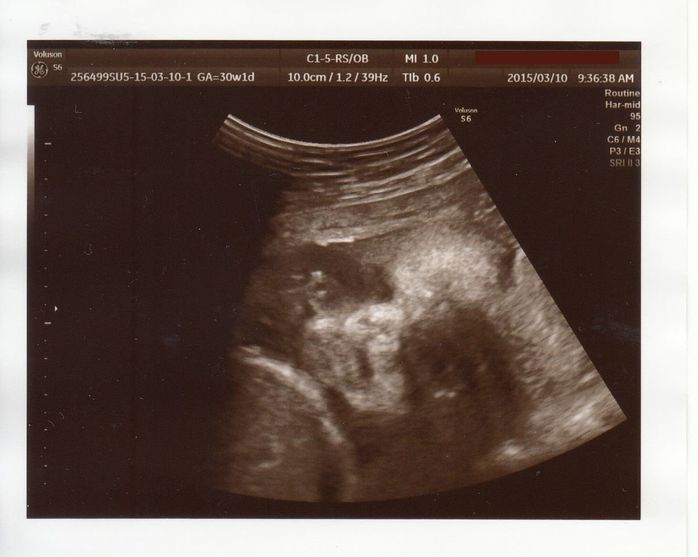

赤ちゃんの体重が少なめだと指摘される - 妊娠30週目のエコー写真

エコーは左下の曲線が頭、真ん中の白っぽいのが手です。おなかの中で、よくしゃっくりをする赤ちゃんでした。しゃっくりをしているときにおなかに触ると、びくっとしているのが分かるので、夫にも触ってもらい、2人で「元気だね」と喜びました。

検診ではエコーで赤ちゃんの太ももの長さと頭の長さを計測して、推定体重を教えてもらっていたのですが、この頃から赤ちゃんの体重が少なめだと医師に言われるようになりました。